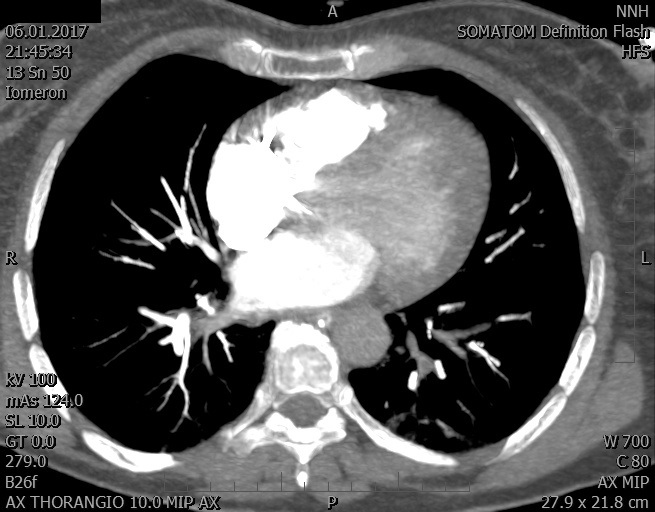

Video 2 - Echokardiograficky byla zjištěna těžká dysfunkce dilatační levé komory s nezvětšenou pravou komorou.Pro nejasnou příčinu zástavy jsme provedli i vyšetření výpočetní tomografií (CT), které vyloučilo plicní embolizaci (série 1 - soubory na konci článku). V den přijetí při přetrvávající oběhové nestabilitě byla nemocná opakovaně defibrilována pro fibrilaci komor se stabilizací rytmu po podání amiodaronu a mesocainu. Dle hemodynamických měření se jednalo o těžký kombinovaný šok. Vstupní laboratorní vyšetření bylo bez větších pozoruhodností. Posléze jsme doplnili anamnézu od příbuzných a zjistili, že pacientka užila do dvou hodin před srdeční zástavou první tabletu amoxicilinu na lehký respirační infekt. Při nevýtěžnosti vstupních vyšetření a nových anamnestických informacích jsme doplnili 14 hodin po kolapsu vyšetření koncentrace tryptázy v séru, která byla extrémně zvýšena (tabulka 2), což nás vedlo k podezření na anafylaxi.